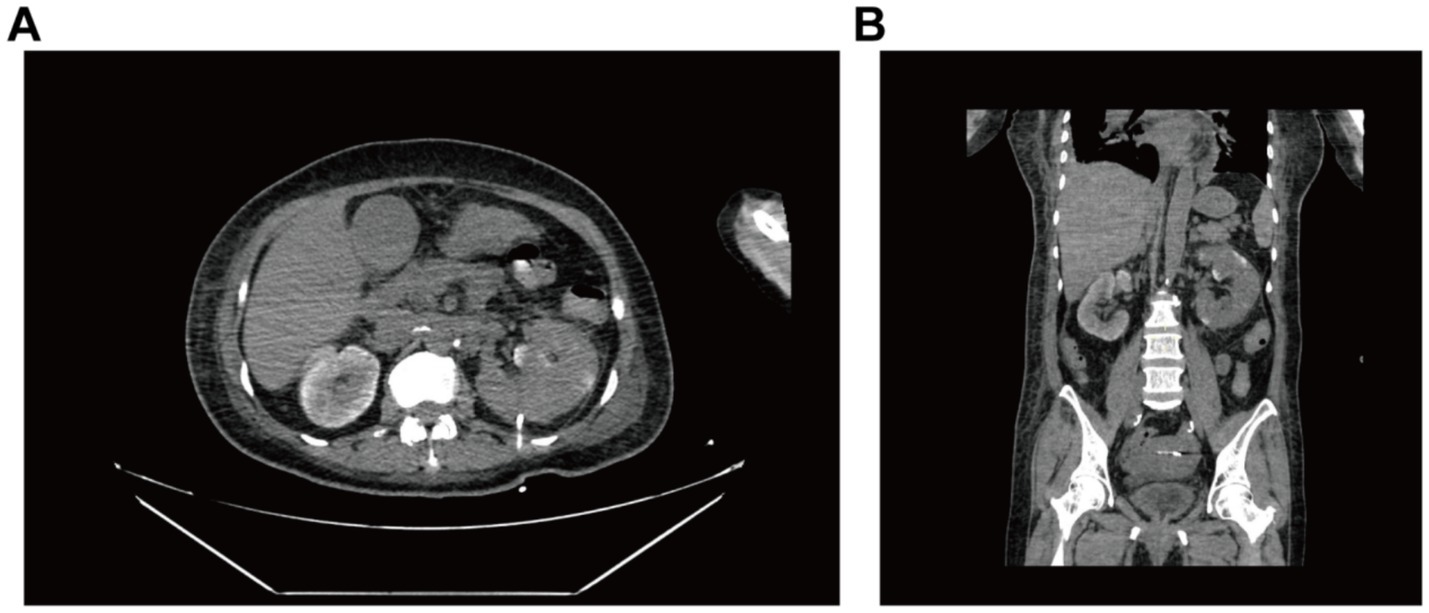

After multidisciplinary consultation, CT-guided percutaneous drainage of the left kidney was performed (Supplementary Figure S1), yielding gas and dark red fluid. Two sets of blood cultures identified gram-negative bacilli, confirming sepsis secondary to EPN, likely due to Escherichia coli. The patient was given treatment of anti-infection with meropenem and blood glucose control. On the 2nd postoperative day, the left renal puncture drainage tube was in position and drained dark red fluid, and the examination was repeated: WBC 9.32 × 109/L, neutrophil 8.03 × 109/L, ultrasensitive CRP 269.15 mg/L, calcitonin 61.49 ng/mL, B-type brain natriuretic peptide 8,490, and creatinine 161.7 μmol/L. Besides, hypoxemia (SpO₂ 91% on 6 L/min O₂) raised concern for respiratory failure. Comprehensive treatment with meropenem (1 g, IVD, q8h) for anti-infection, insulin pump for glycemic control, and furosemide for diuresis to improve cardiac function was given. Repeat CT plain scan of the whole abdomen demonstrated reduced gas but persistent perirenal inflammation (Figure 2). On postoperative day 5, the drainage volume decreased and presented as pale sanguineous fluid. Blood cultures (aerobic) identified Escherichia coli. The current antimicrobial therapy was continued in accordance with the susceptibility profile (see Supplementary Table S1) with close monitoring of body temperature and serial inflammatory markers.

Figure 2. CT-guided whole-abdomen CT plain scan reviewed 2 days after renal puncture and drainage. Both (A) axial and (B) coronal images demonstrate mild left renal enlargement with perirenal exudation complete resolution of previously seen pneumatosis.